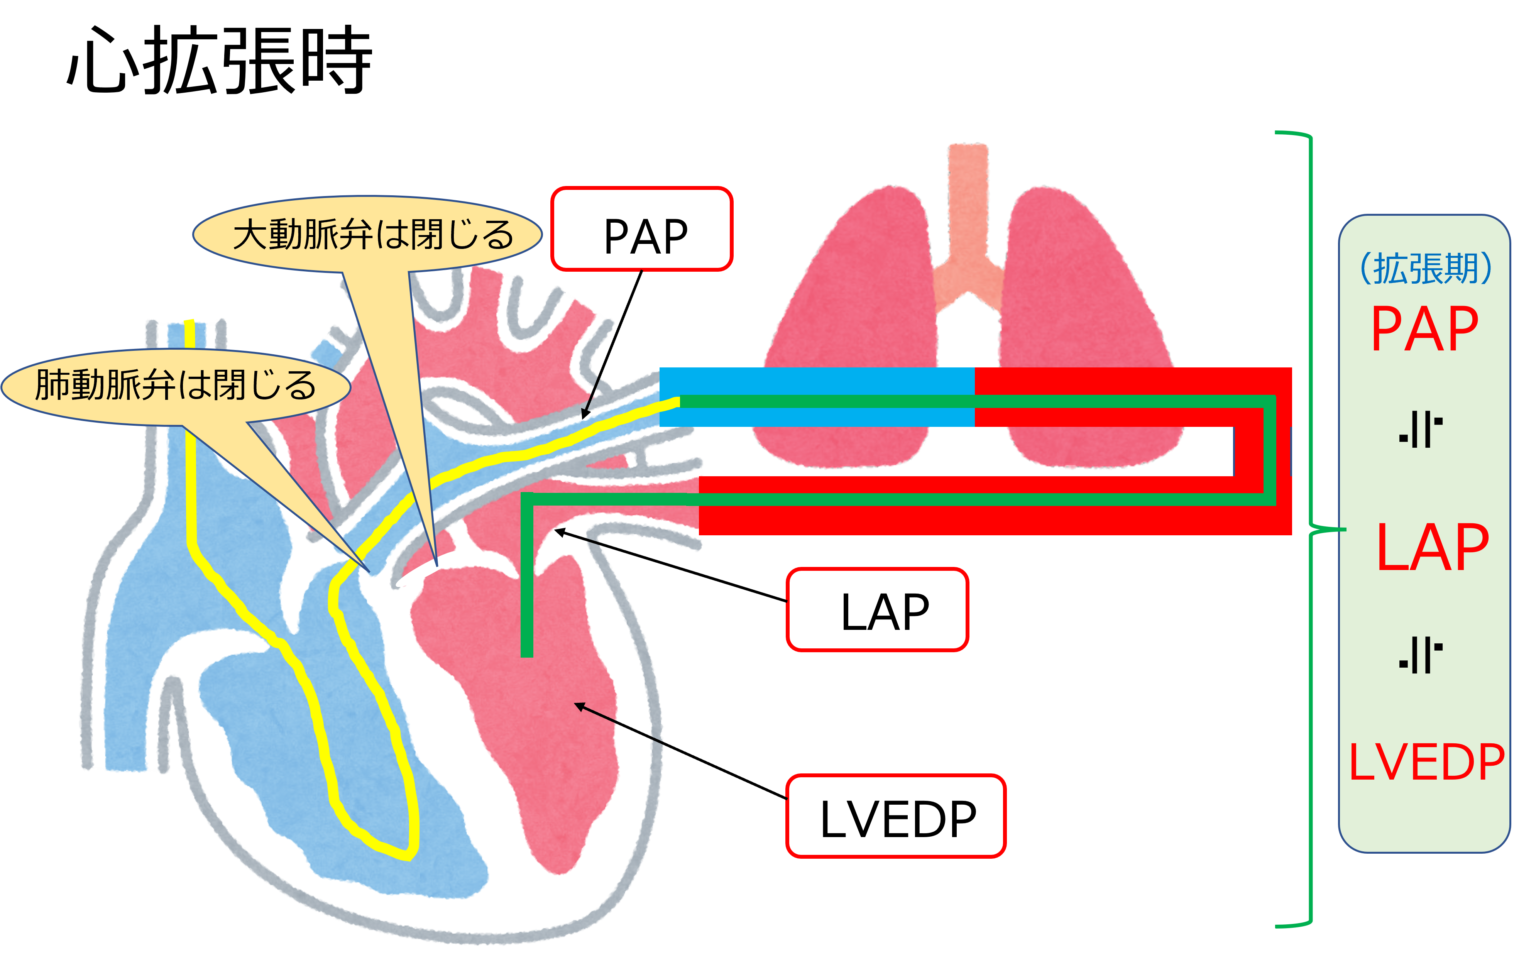

この処置自体は、右心カテーテル法と呼ばれることもあります。これは、心臓の右側を流れる血液の圧力を測定できるためです。 3 つの異なる場所で圧力を測定します。

- 肺動脈

- 肺毛細血管

これらの測定値は、心臓の適切な部分の血液中の酸素量を把握するために使用できます。また、心臓から全体的にどれだけの血液が流出するかを把握するためにも使用されます。